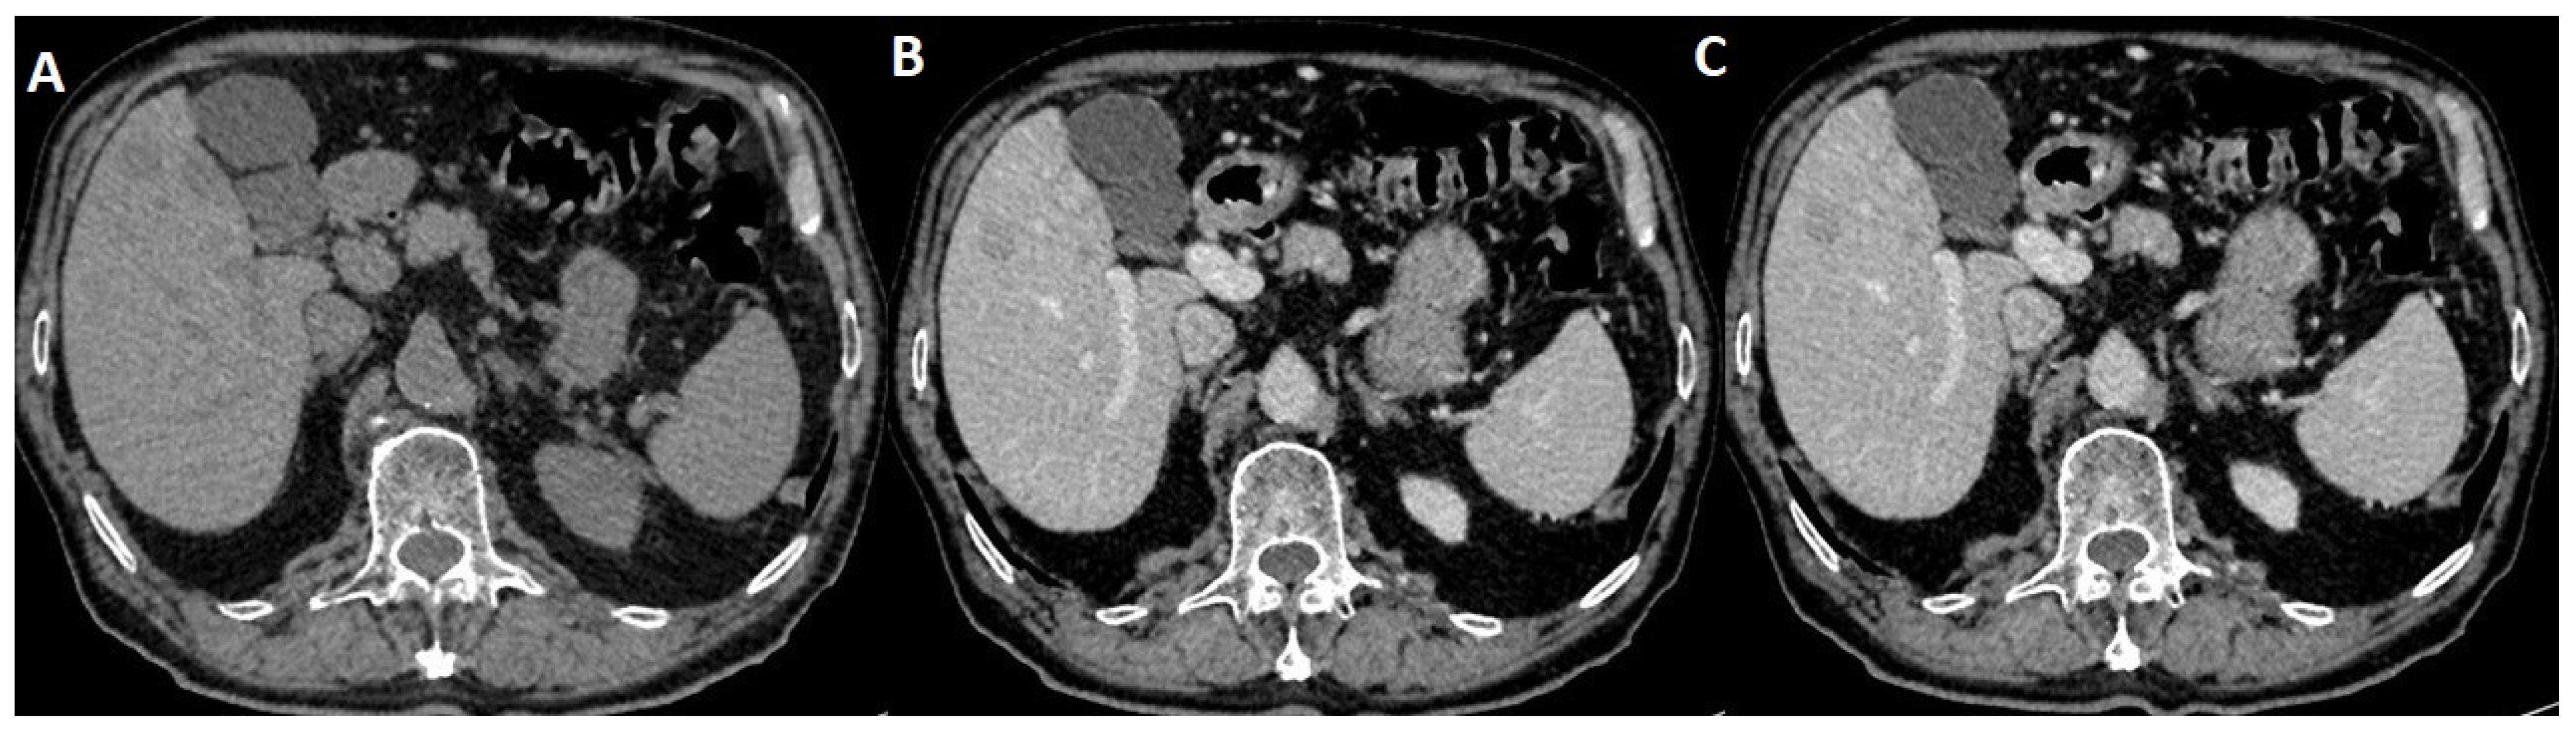

2.4. Delayed Multiphase Scanning